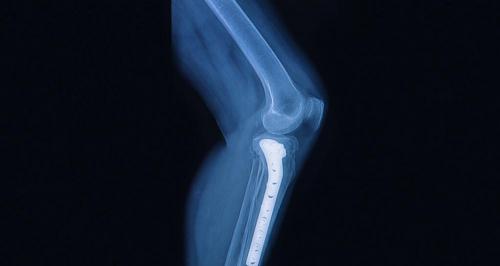

我在之前的文章《路医生说丨放在身体深部的钢板钉子,有些,真的可以不用取 》中,告诉大家很多深部的钢板是可以不取的,甚至是千万别取的。这篇文章发表后,无论是评论区还是后台私信,都有很多朋友在询问,自己做的手术放入的具体的内固定到底要不要取。由于没有时间挨个回答,所以今天咱们就索性用这篇文章统一解答下。

取出后特别容易再次骨折的,最典型的就是前臂尺桡骨骨折钢板固定,如果并不影响前臂旋转活动,一般建议都是最好别取了。